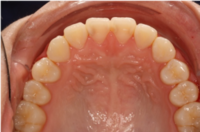

Foto skeletal utveckling

Profilröntgenbild och konventionell kefalometri.

Foto: Maria Ransjö